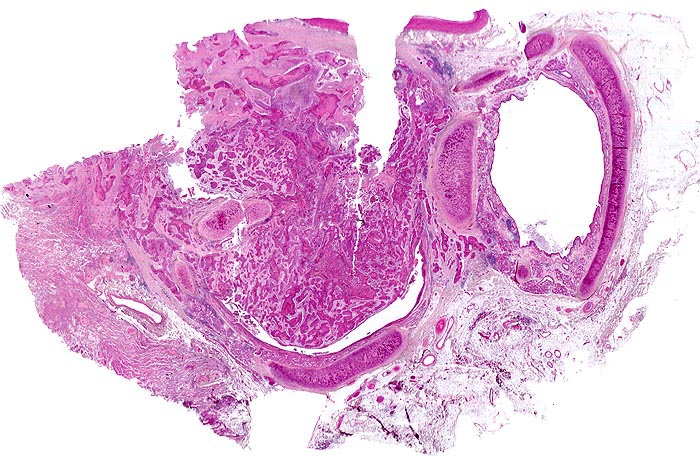

Plattenepithelkarzinom

Lunge

Eine Bronchuslichtung von einem Tumorzapfen weitgehend verschlossen. Rechts davon ein tumorfreier Bronchusquerschnitt. Das Tumorgewebe bildet solide Zellstränge, welche eingebettet sind in ein desmoplastisches Stroma. Zusammengequetschtes Lungengewebe am Rand der Probe.

Zentrales Bronchuskarzinom des rechten Lungenoberlappens von 5cm Durchmesser. Lungenoberlappenresektion.

Das Präparat zeigt den tumorbefallenen Bronchusresektionsrand. Die Resektion erfolgte also nicht im Gesunden.